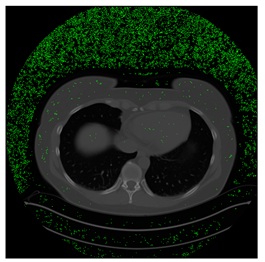

Table 5. Testing results of the Lung-PET-CT-Dx database.

Lung-PET-CT-Dx Computers 10 00152 i028 Computers 10 00152 i029 Computers 10 00152 i030

BPP0.05PSNR61.01Modified BPP0.052